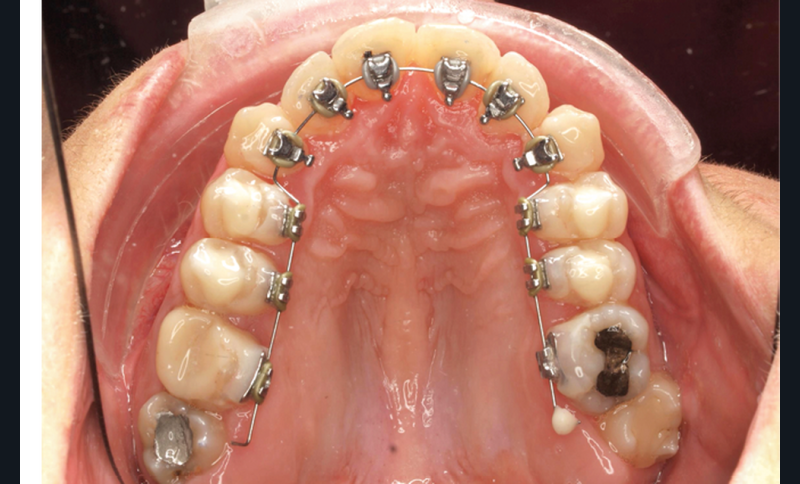

- Premier rendez-vous (fig. 2a) : l’arcade maxillaire est appareillée et un arc NiTi .014 en expansion est placé. L’arcade mandibulaire reçoit des cales rétro-incisives pour lever l’occlusion inversée. Par confort, des cales prémolaires, sans contact avec les dents antagonistes, sont posées pour réduire l’inocclusion latérale.